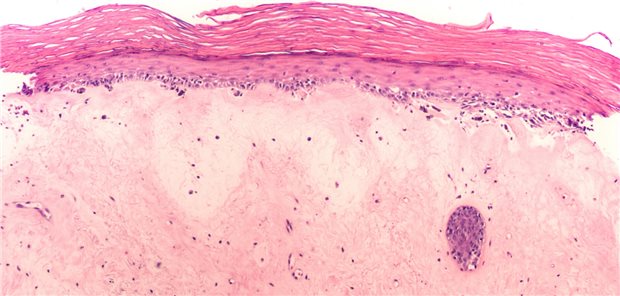

Neue S3-Leitlinie veröffentlicht

Lichen sclerosus erkennen und leitliniengerecht therapieren